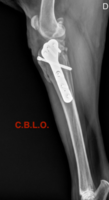

¿POR QUÉ ES IMPORTANTE EL LIGAMENTO CRUZADO ANTERIOR ( LCA)? La rodilla consta de 4 ligamentos que “sujetan” los dos huesos de la articulación: fémur y tibia. De todos ellos, el más importante para el funcionamiento de la rodilla es el LCA. Si éste sufre una rotura, ya sea total o parcial, la estabilidad se ve comprometida y por una serie de fuerzas musculares (la fuerza resultante se llama “empuje tibial”) la tibia se desliza y arrastra sobre el fémur . Las causas de esta rotura pueden ser traumáticas ( sobre todo giros forzados, caidas, arrancadas, etc) o más frecuentemente, degenerativas ( el LCA va perdiendo aporte sanguíneo con la edad y acaba “deshilachándose” poco a poco hasta que acaba rompiendo). Independientemente de la causa, el resultado final es una artrosis al alterarse la biomecánica de la rodilla. De hecho, la rotura del LCA es la causa más frecuente de artrosis de rodilla. ¿COMO SABER SI MI PERRO TIENE UNA ROTURA DEL LCA? La cojera es el síntoma más característico, y dependiendo del grado de rotura, puede variar desde una cojera leve a una cojera de no apoyo. Incluso en casos muy iniciales el único síntoma puede ser un pequeño cambio postural en la forma de sentarse o de incorporarse, ya que éstos animales no pueden flexionar (doblar) la rodilla completamente. Los animales afectados son de cualquier tipo de raza y edad. En nuestro Centro la raza más comúnmente afectada es el Boxer, seguido del Golden Retriever , Bulldog, y también perros de raza pequeña ( Caniches, Yorkshires, etc) Es bastante frecuente que el ligamento no rompa completamente, sino que sólo algunas fibras estén dañadas ( es decir, una rotura parcial del LCA). A veces, ni el mismo propietario del perro se da cuenta de que éste cojea, ya que no lo hace todos los días ni a todas horas, y puede ser muy leve. ¿QUE PRUEBAS LE HARAN A MI PERRO PARA DIAGNOSTICAR LA ROTURA DEL LCA? El diagnóstico si la rotura es completa es muy sencillo. Con técnicas de palpación bajo anestesia o sedación ( test de compresión tibial y test del cajón), demostraremos el movimiento de traslación craneal tibial ( es decir, la tibia se desplaza hacia delante cuando la empujamos). Si estos test son positivos, el diagnóstico es de rotura del LCA. En las roturas parciales, ese movimiento de traslación puede no estar tan claro o incluso no existir, si una gran parte del ligamento todavía está intacta. En estos casos, el traumatólogo valorará también la radiografía de la rodilla, para detectar signos de artrosis ( ya habíamos visto que la rotura del LCA causa inevitablemente artrosis), que pueden aparecer ya al mes de la rotura. En otros casos, también se recomienda hacer una artrocentesis ( punción del derrame articular) y posterior análisis de ese líquido , que puede ayudar a esclarecer las causas de la lesión de rodilla. Otras técnicas que son útiles para el diagnóstico son la Resonancia magnética o la artroscopia. Esta última tiene la ventaja de que en caso de confirmar la lesión, se puede intervenir al animal en el mismo acto quirúrgico. ¿TIENE SOLUCIÓN LA ROTURA DEL LCA? Generalmente la solución pasa por una intervención quirúrgica. Algunos casos se pueden tratar de manera conservadora (si la cojera no es muy marcada), con antiinflamatorios y reposo indefinidos. Esta es una opción reservada para animales menores de 10 Kg. Los problemas que puede acarrear son fundamentalmente que la rodilla sufrirá una artrosis que avanzará más rápidamente que si se operara, que la cojera puede persistir indefinidamente, y que los meniscos pueden lesionarse fácilmente ( los meniscos son unos anillos de cartílago dentro de la rodilla que actúan como “amortiguadores” cuando el perro camina, y que se dañan con facilidad cuando rompe el LCA) Con respecto al tratamiento quirúrgico, hoy en día se utilizan generalmente técnicas basadas en osteotomías tibiales. Esto quiere decir que para reparar el LCA, después de explorar la articulación y los meniscos, se realiza un corte (osteotomía) en la tibia , en forma de cuña ( Técnica T.W.O.), semicircular ( Técnica T.P.L.O.), o vertical ( Técnica T.T.A.). Una nueva técnica (C.B.L.O.) utiliza un corte semicircular invertido y muestra resultados muy prometedores. Con estas osteotomías se consigue variar la biomecánica de la rodilla de forma que el LCA no sea imprescindible para caminar, correr, saltar, etc. Esa osteotomía luego se fija con una placa y tornillos especiales, que no es necesario retirar del hueso. Con estas técnicas los resultados son óptimos para la funcionalidad de la rodilla, con buen movimiento articular, control de la artrosis, recuperación rápida y completa de la cojera, etc Otro tipo de técnicas que van cayendo en desuso son las llamadas técnicas extraarticulares. Consisten en colocar una especie de ligamento artificial muy básico (unos filamentos de poliamida o cerclaje quirúrgico) que unan la tibia y el fémur, para imitar la sujeción de la rodilla que proporcionaba el LCA. No es una técnica tan avanzada como las anteriores y los resultados son más modestos. Además, en ocasiones el filamento puede romper a su vez, causando una reactivación de la cojera en algunos casos.Con uno u otro tipo de técnicas, es importante que los meniscos se exploren y se retiren en caso de que hayan sufrido alguna lesión, ya que si no se hace, pueden a su vez causar más cojera y más artrosis. La no retirada de los meniscos enfermos es una de las causas más frecuentes de malos resultados de la cirugía de LCA, por lo que se le está prestando mucha atención en la actualidad, pudiendo hacerse incluso por vía artroscópica, sin abrir la rodilla más que en dos pequeños puntos. En nuestro Centro para extraer los meniscos enfermos usamos la "miniartrotomía pararrotuliana medial", técnica que permite la extracción con una incisión en la cápsula articular de unos 2-3 cm. solamente ¿QUE SECUELAS PUEDE DEJAR LA ROTURA DEL LCA? Los animales intervenidos una vez transcurre el periodo de rehabilitación pueden llevar una vida normal, con saltos, carreras, etc. La única limitación la causa la artrosis, que como ya hemos visto afecta a la mayoría de las rodillas con rotura del LCA. Además, con cierta frecuencia, la otra rodilla puede romper también el LCA, y para evitarlo en estos animales se debería controlar el peso corporal y limitar ciertos tipos de ejercicio intenso